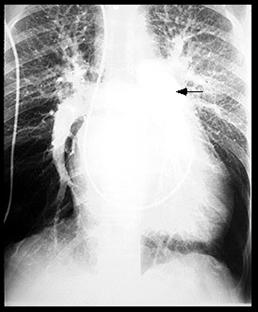

Imagine radiologica de HTPS (DVPA) Imagine radiologica de HTPS (stenoza mitrala)

HTP secundara incipienta (DSA) HTPS severa (DSA Eisenmengerizat)

Imagine Rx. de profil cu HVD Aspect CT de HTP primara